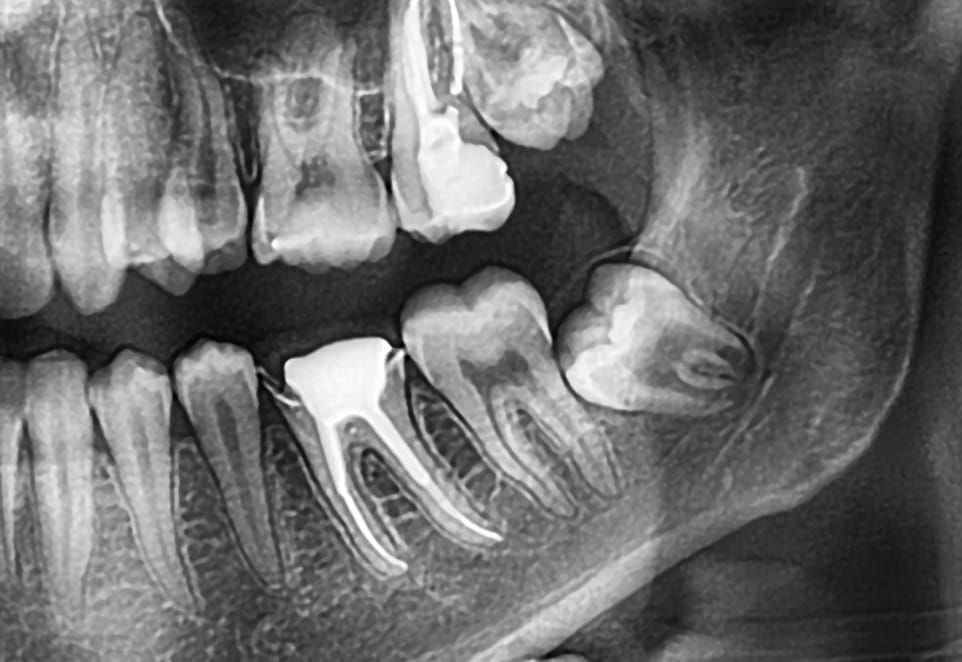

Your wisdom teeth are the final four molars to erupt at the back of your mouth. You have one on each side of your upper and lower arch. Some people find their third molars erupt normally and cause no problems. For others, their wisdom teeth may partially or not erupt at all, which can lead to wisdom teeth pain.

One potential problem occurs when a wisdom tooth become impacted. Impacted teeth can sometimes lead to infection, requiring professional wisdom tooth infection treatment to prevent further complications.

When a tooth is impacted, it can cause the following issues:

- Grows up or down but is still trapped in your jawbone

- Grows at an angle toward the back of the mouth

- Grows at an angle toward the adjacent tooth, your second molar

- Tries to erupt at a right angle so it may come through your gum sideways

If you are a regular patient, we will monitor the location of a wisdom tooth that have yet to erupt. Digital dental X-rays show us the position of these teeth in your jaws and let us determine if they can come through problem-free. We wouldn’t recommend their removal unless it is clear they will cause problems or have already begun to do so.